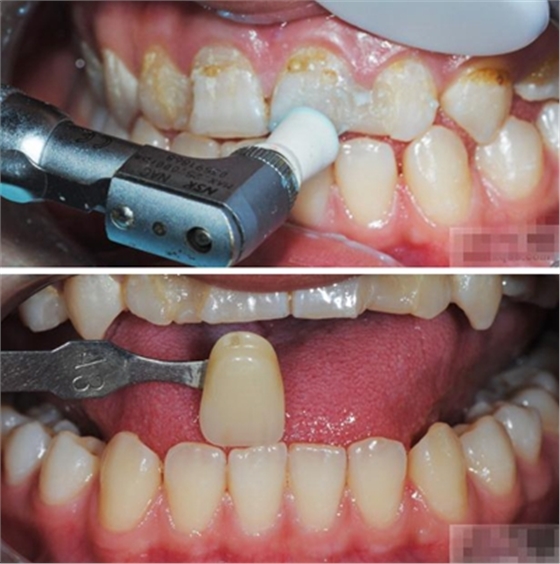

【比色】清潔牙面

比色

談到比色 要考慮天然牙:亮度 、飽和度、色相 、透明度、半透明度 ····

天然牙色彩信息——亮度

天然牙信息——飽和度

透明性和不透明性

合適的透明性很重要

適度則生動(dòng)

太透則灰暗

不透則死板

比色注意點(diǎn):自然光和人造光:

1.自然光的變化較大,陰天太陽升起之后及落下之前3H 最佳

2.朝北的窗下(北半球)

3.人造光源可以采用,了解患者生活環(huán)境推薦使用多種光源下表現(xiàn)的最佳的色片(因?yàn)槿瞬豢赡苤辉谝环N光源下生活)自然光 熒光燈 白熾燈 特殊舞臺(tái)燈光等